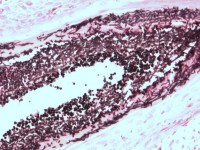

Ook een biopt kan de diagnose aantonen, hierbij zijn schimmeldraden en/of gistbolletjes

te zien in de haarfollikel (PAS kleuring). Bij oppervlakkige mycosen met randschilfering

![Histologie van dermatomycosis barbae, tinea barbae (click on photo to enlarge) [source: www.huidziekten.nl] Histologie van dermatomycosis barbae, tinea barbae](../../../images/dermatomycosis-barbae-PA-4z.jpg) |

![Histologie van dermatomycosis barbae, tinea barbae (click on photo to enlarge) [source: www.huidziekten.nl] Histologie van dermatomycosis barbae, tinea barbae](../../../images/dermatomycosis-barbae-PA-5z.jpg) |

![Histologie van dermatomycosis barbae, tinea barbae (click on photo to enlarge) [source: www.huidziekten.nl] Histologie van dermatomycosis barbae, tinea barbae](../../../images/dermatomycosis-barbae-PA-6z.jpg) |

| mycose

baardstreek (PA) |

PAS kleuring |